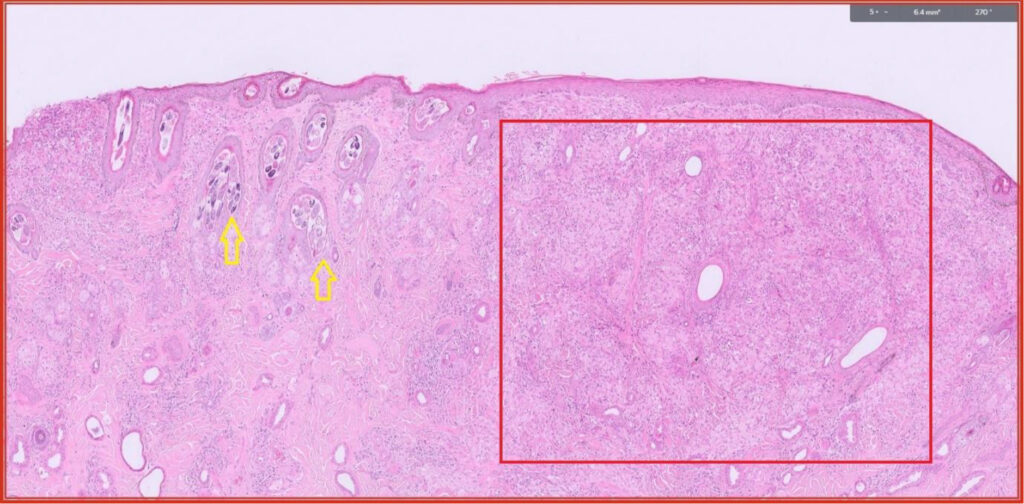

Fig 5. Feline skin. This cat was unlucky as it had two separate skin diseases. Yellow arrows (see Fig 6). Red box – this is hypercellular dermis due to pyogranulomatous inflammation (see Figs 7 and 8).

Fig 6. Myriad Demodex mites in multiple hair follicles.